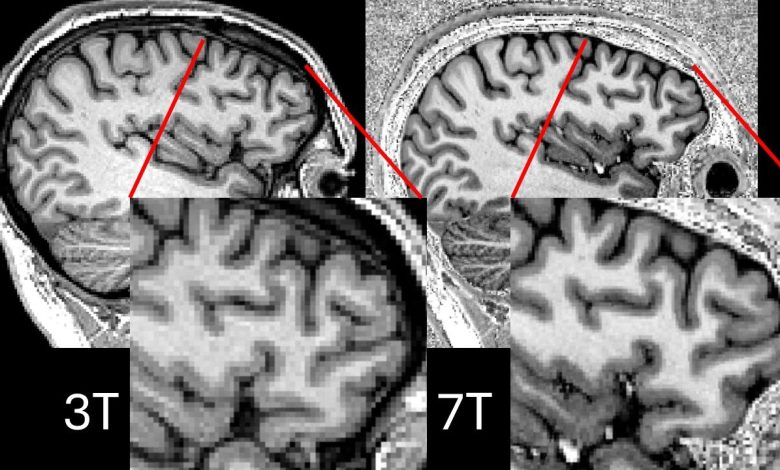

Comparação mostrando varreduras 3T e 7T para o mesmo participante. Crédito: P Simon Jones, Universidade de Cambridge

Anteriormente, os scanners de ressonância magnética 7T-tão chamados porque operam usando um campo magnético de 7 tesla, mais que o dobro da força dos scanners 3T anteriores-sofriam de manchas negras de sinal nas partes cruciais do cérebro. Mas em pesquisas publicadas em EpilepsiaPesquisadores de Cambridge e Paris usaram uma técnica que supera esse problema.

Os scanners de ressonância magnética ultra-alta do campo 7T permitem uma resolução muito mais detalhada nas varreduras cerebrais e demonstraram em outros países que são melhores do que os melhores scanners de ressonância magnética 3T do NHS na detecção dessas lesões em pacientes com epilepsia resistente a medicamentos (e, de fato, os hospitais do NHS têm mais fracos, 1.5 Teclans).

No entanto, as varreduras de ressonância magnética 7T são suscetíveis a manchas escuras conhecidas como queda de sinal. Esses desistentes geralmente ocorrem nos lobos temporais, onde a maioria dos casos de epilepsia surge.

As imagens paralelas de transmissão 7T eram mais claras que as imagens convencionais (‘transmissões únicas’) 7T em mais da metade dos casos (57%) e, nos casos restantes, as imagens eram igualmente claras. Os scanners de transmissão única nunca superaram os scanners de transmissão paralela.